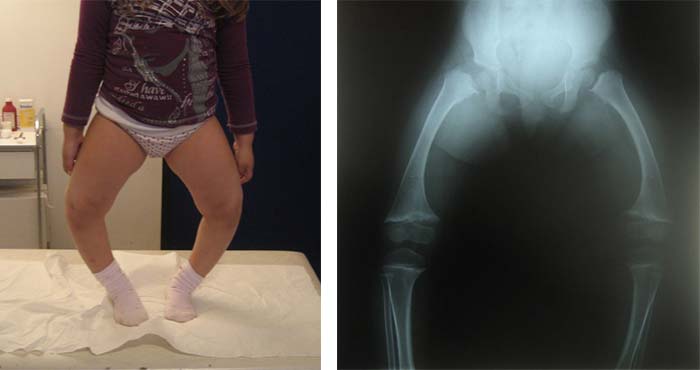

Οι διαταραχές του μεταβολισμού του ασβεστίου, συνήθως νεφρογενούς αιτιολογίας, οδηγούν στην καθυστέρηση της επασβέστωσης στα αναπτυσσόμενα οστά, με δημιουργία παραμορφώσεων στα κάτω άκρα, συνήθως ραιβογονίας και σπανιότερα βλαισογονίας.

Η εμφάνιση σημαντικής ραιβογονίας, σε παιδιά με χαμηλό ύψος και ευκαμπτότητα, πρέπει άμεσα να ελέγχεται. Η χαρακτηριστική ακτινολογική εικόνα με διεύρυνση της επιφυσιακής πλάκας, είναι παθογνωμονική.  Η φαρμακευτική αντιμετώπιση μπορεί να βελτιώσει την εικόνα των άκρων, σε αντίθεση με την χειρουργική διόρθωση που όταν γίνεται ΧΩΡΙΣ φαρμακευτική υποκατάσταση, υποτροπιάζει άμεσα.

Εικόνα βαρύτατης νεφρογενούς ραχίτιδος. Αρχική εικόνα ραιβογονίας με την ακτινολογική εικόνα.